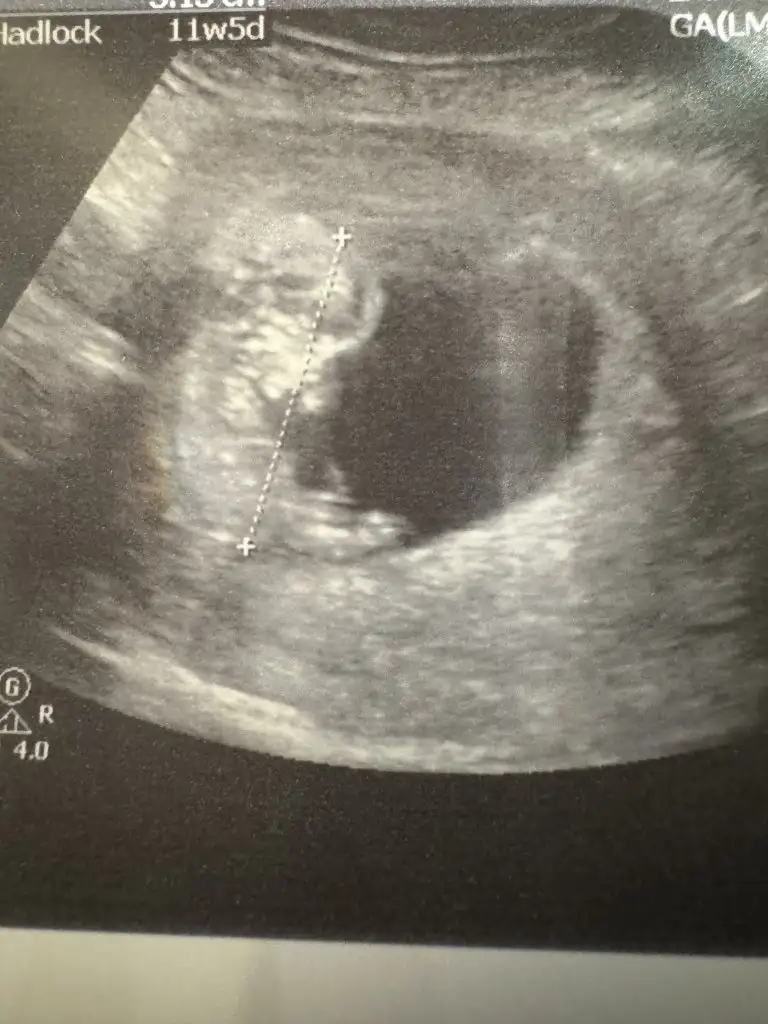

Şu an itibariyle 12+4 teyiz. Fetal yaptırmadık dün ikili teste girdim. Ense kalınlığı 0,95 çıktı burun ve alın kemikleri de mevcut. Kol ve bacaklarını yukarıya doğru uzatmış uyuyordu bizimki. O yüzden bacak arasını görmek zor olmadı. Doktor birkaç kez gösterip bacak arası boş ama şimdilik kız da erkek de diyemem dedi (ben kız isteyip hissediyorum başından beri).

Yaa duruşa bak maşallah bencede erkek gibi heybetli duruşu var Allah nazardan saklasınİyi haberlerle geldim kızlar bendeÇok şükür bebek iyiymiş içeride. Her şey yolundaymış Ense kalınlığı, burun kemiği her şey iyi çıktı. Cinsiyeti en erken 2 hafta sonra belli olurmuş. Var mı içine doğan cinsiyet konusunda tahmini olan Baksanıza içeride kara kara düşünüyor sanki Eki Görüntüle 3533578